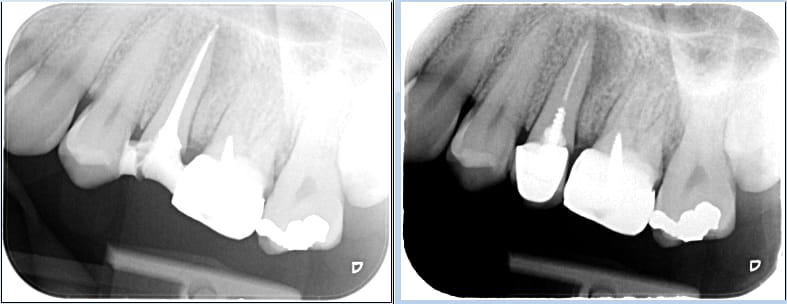

la seule chose que je peux te dire et qui est en rapport avec la paupérisation et le vieillissement de la population française c'est que pour le patient avec lequel j'ai illustré mon précédent post 5800e ca doit représenter 3 années de reste a vivre. Tu as bien choisi ton camp camarade.